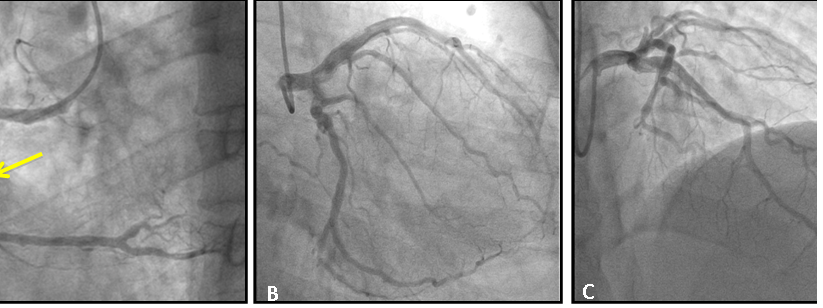

Figure 2 (A) Right coronariography in left oblique projection demonstrating occlusion of right marginal branch in proximal segment (arrow); (B) left coronary angiography in caudal projection; C: left coronary angiography in cranial projection; both showing no significant obstructive lesions in the other coronary arteries.

Figure 5 (A) right coronary angiography in left oblique projection demonstrating total occlusion of the non-dominant right coronary in its proximal portion (arrow); (B) left coronary angiography in direct cranial projection demonstrating mild obstructive lesion in diagonal branch; (C) left coronary angiography in right obliquous projection demonstrating dominant circumflex branch with mild obstructive lesion in its proximal portion.